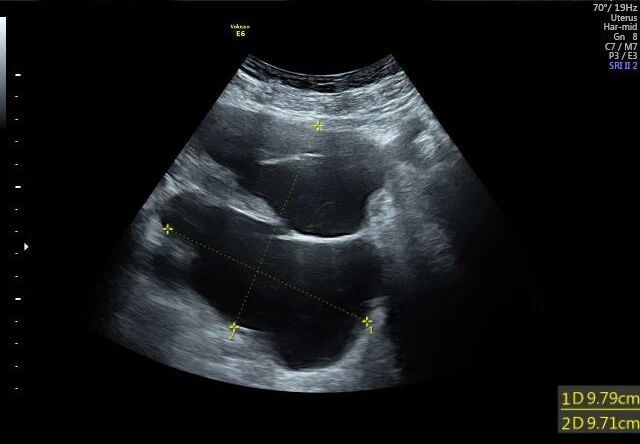

1. 超声检查:首选且最常用的检查。B超下可见盆腔内囊性无回声区,边界多不清晰,形态不规则,囊壁薄而模糊,内部无血流信号,结合患者有手术史或盆腔炎病史,可初步诊断。

图片